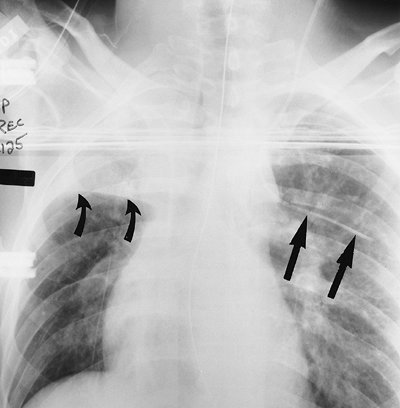

FIGURE 5-5. Intercostal vein placement of central venous catheter. Anteroposterior (AP) recumbent chest radiograph shows the left jugular central venous catheter crossing to the left and coursing horizontally, inferior to the left fifth posterior rib, typical of intercostal vein placement (straight arrows). The intercostal vessels and nerves are inferior to the rib; when performing thoracentesis, the needle should be inserted along the top of the rib to avoid puncturing these vessels. Note collapse of the right upper lobe, with superior displacement of the minor fissure (curved arrows).